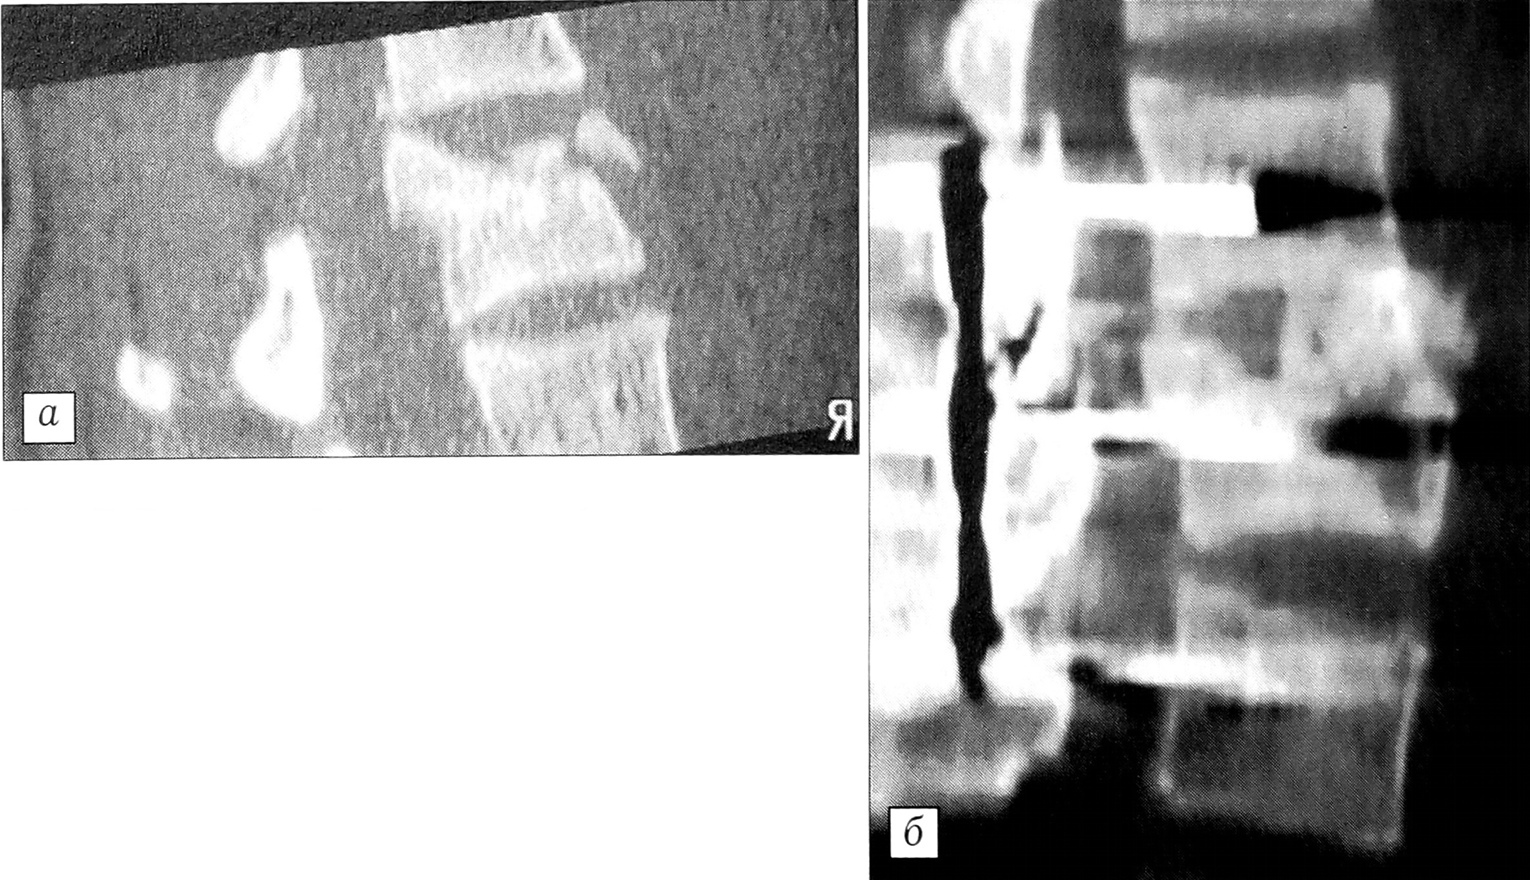

Если мы хотим достичь уровня T12-L1 (рис. 5), спицы Steinmann должны быть установлены на более высоком уровне для эффективного смещения содержимого брюшного мешка. По нашему опыту, левая ножка диафрагмы легко определяется, она не служит препятствием для переднелатерального левого доступа к позвоночнику, но при необходимости может быть пересечена после предварительного гемостаза. На этом этапе — перед началом удаления диска или корпорэктомии — делают снимки в передней и боковой проекциях. Поясничный валик фиксирован в определенном положении.

Рис. 5. Доступ к уровням выше L2.а — футляр прямой мышцы живота рассечен латерально слева; б — положение селезенки и почки при доступе к уровню L1; в — разрез левой ножки диафрагмы для подхода к переднебоковой поверхности позвоночника; г — кожный разрез (обратить внимание на наличие старого рубца после трансперитонеальной операции на желудочно-кишечном тракте, что не вызвало никаких проблем).